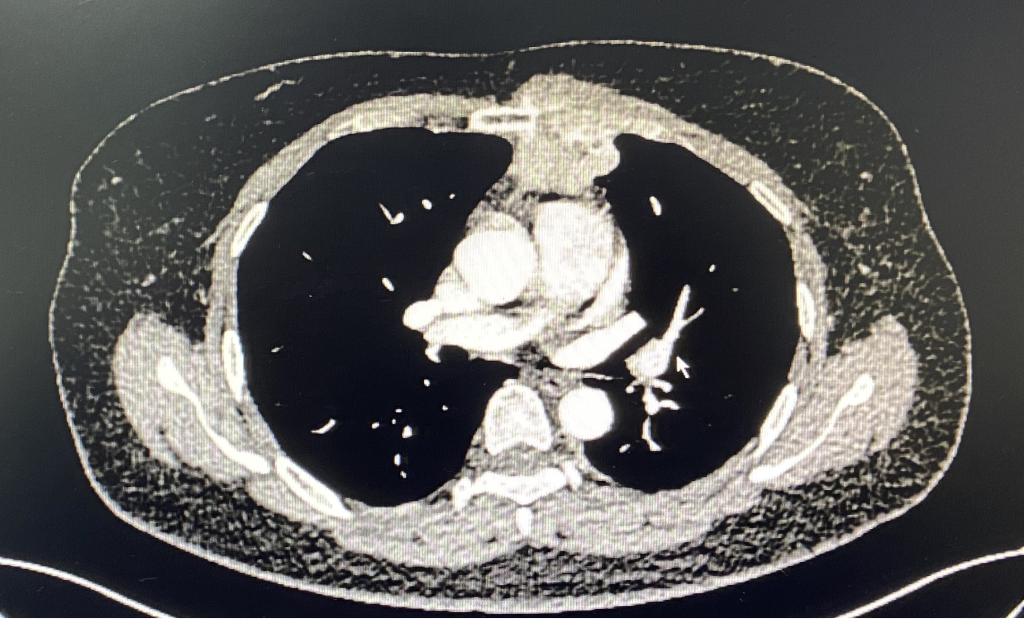

病例2:术前胸部增强CT

另一位女性患者发现左前胸壁肿物1周就诊,胸部CT示胸壁及前纵隔可见不规则软组织密度影,大小约48mmx40mm,长径约10cm,病灶与临近胸骨及左侧第2、3肋软骨分界不清。行超声引导下肿物穿刺活检,病理显示间叶来源肿瘤。肿瘤突破纵隔,侵犯了部分胸骨、左侧肋软骨以及胸部肌肉组织,此类型病例较少见,需切除部分受损胸骨及肋软骨,并对缺损的胸壁进行重建。由于缺损处较大,合适胸肋骨重建材料(如相应钢板和3D打印材料)价格昂贵,病人经济状况不能承担,李少民主任利用现有的胸骨钢板、肋骨环抱器以及经李少民主任改良的勾状的肋骨环抱器进行拼接,解决了长度的问题,稳定性上也表现出色,完美地重建了胸廓的完整性。手术入路也开创性的选择了胸腔镜和传统开胸手术结合的方式,从剑突下进行微创手术游离肿瘤的两侧及基底部,再从左侧胸壁开口,完整切除胸壁受侵组织,然后像打开“盖子”一样,移除肿瘤,避免了正中劈开胸骨的巨大创伤。手术过程顺利,术后恢复良好。